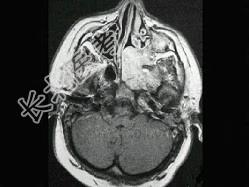

- 单项选择题男性,19岁, 左侧鼻腔反复出血一年余,CT、MRI扫描如图所示, 请选择最可能诊断 ( )

C、鼻咽部青年纤维血管瘤